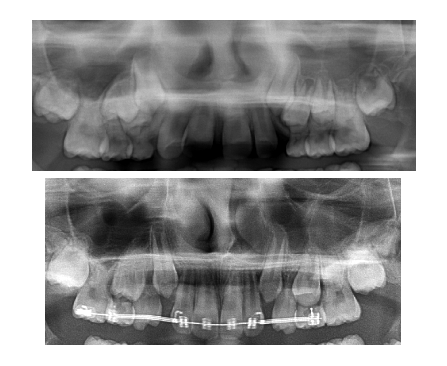

Lenk Orthodontics produces beautiful smiles. More importantly, the goal is to prevent problems before they happen…THIS IS A GREAT EXAMPLE…

EXCESS SPACING WAS NEGATIVELY IMPACTING THE DEVELOPMENT AND ERUPTION OF PERMANENT TEETH IN THE BONE…A LITTLE BIT OF EARLY CARE PREVENTED DAMAGE TO ROOTS, ECTOPIC ERUPTION, AND IMPACTION OF TEETH (IN SHORT, ALOT OF TIMELY AND EXPENSIVE TREATMENT AT THE AGE OF 13!!!)